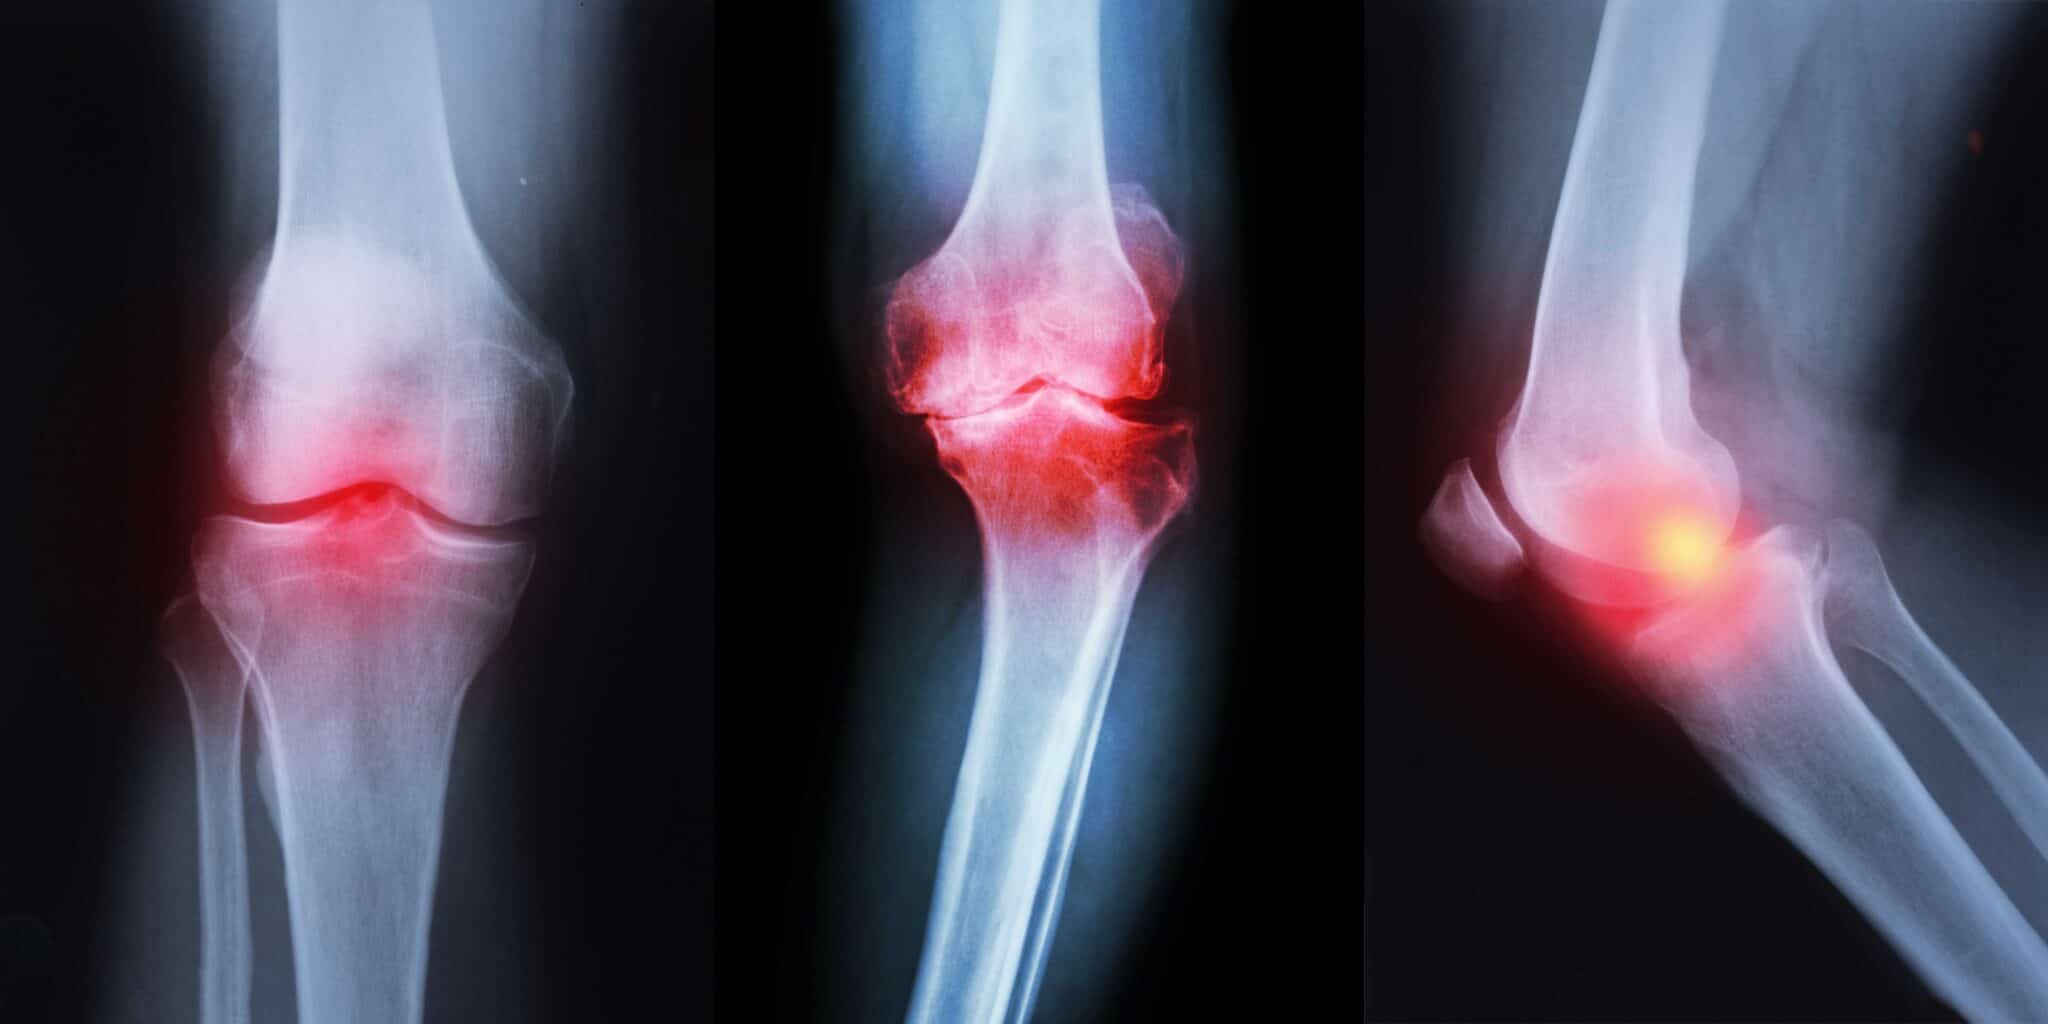

Can Knee Arthritis Cause Shin Pain . Arthritis is inflammation of one or more of your joints. Because of its complex range of motion and the weight that’s often distributed through the joint, the knee is vulnerable to injury. Arthritis is a leading cause of pain and disability worldwide. Arthritis in the leg can cause pain anywhere from the top of the thigh to the ankle. Your provider may also take and analyze fluid from your joint to rule out other causes of knee pain or other forms of arthritis. Pain, swelling, and stiffness are the primary symptoms of arthritis. You can find plenty of advice about easing the pain of arthritis and other conditions. Shin pain can result from various conditions, such as shin splints, stress fracture, peripheral neuropathy, or spinal problems. It may interfere with daily activities, such as climbing. It can develop as a result of various forms of arthritis, which cause inflammation. According to the arthritis foundation, arthritis may cause a person to experience pain, stiffness, and swelling in the knee. Learn about the symptoms, diagnosis, and.